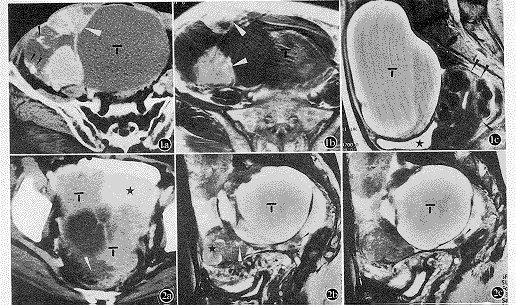

CT、MRI、CT加MRI影像诊断三特性的结果详见表2。差异有显著性(P<0.05或P<0.01)的项目仅有侵犯包膜之准确性(CT与MRI,P=0.012;CT、MRI、CT加 MRI,P=0.008)和肠系膜病变之敏感性(CT与MRI,P=0.015;CT、MRI、CT加MRI,P=0.007),其余差异均无显著性(P>0.05)。根据CT、MRI及CT加MRI影像诊断而准确分期的情况为:Ⅰa期分别为14,12及10例,Ⅰc期各为 2例,Ⅱc期各为 2例,Ⅲc期各为 10例 (图1,2 )。分期不符的情况为:将Ⅱb分为Ⅰa 在MRI有2例,分为Ⅱa在 CT及CT加MRI各有2例;将Ⅲb分为Ⅰa在CT有2例,分为Ⅰc在MRI有2例,分为Ⅱb分别有2,4及4例;将Ⅲc分为Ⅱa 各有2例,分为Ⅱc在MRI有2例,分为Ⅲb在CT及CT加MRI各有2例。CT、MRI和CT加MRI的准确性分别为73.7%、68.4%和70.6%,在统计学上差异无显著性(P>0.05)。

从比较结果看,仅包膜受侵的准确性(CT、MRI、CT加MRI分别为73.7%、94.7%、94.1%)和肠系膜病变的敏感性(72.7%、12.5%、80.0%)差异均有显著性(P<0.05或0.01),前者是CT偏低,后者主要为MRI较差所致。然而其余虽在统计学上差异无显著性 (其中可能与项目样本数偏少有关),但由表2仍可见,在单侧或双侧肿物和腹膜种植灶,CT要优于MRI,主要是敏感性较高,这是由于CT的空间分辨率高及运动伪影少,能较清楚显示系膜结构、钙化、肠管结构及他们之间的解剖关系。而MRI显示侵犯包膜 (除上述准确性外)、侵犯除肠管以外的盆腔脏器、子宫直肠窝病变及淋巴结转移的三特性,多数要高于CT,这主要是因为MRI具有多方位及多参数(T1、T2权重像及增强)成像的优点,更好地显示了盆腔脏器解剖关系和肿瘤本身。